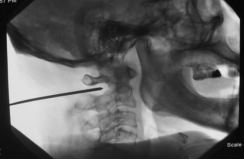

3.微创治疗:阻滞疗法(枕神经阻滞、C2背根神经节阻滞)、射频治疗(C2背根神经节脉冲射频、C3脊神经后支射频、枕大小神经射频)和电刺激治疗(周围电刺激术、脊髓电刺激术),听到微创治疗不要紧张,都是局部麻醉,在颈部打个小针就可以了。